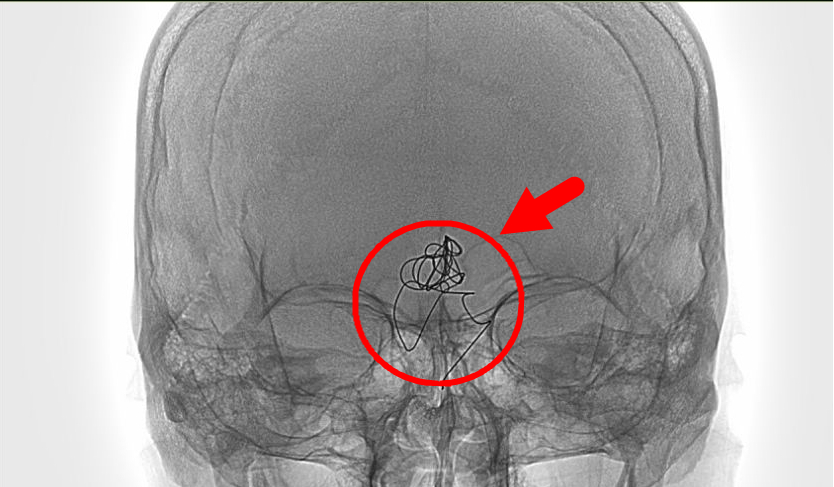

当检查画面映入眼帘时,惊呆了在场的所有人,第一次手术填塞的金属弹簧圈,已经因为动脉瘤的扩张,变成一堆杂乱无章的铁丝线排列在李先生的脑子里。造影后的图像更是让人咋舌:一个 10*30 mm 巨大的夹层动脉瘤盘踞在脑干的前方,而且基底动脉异常的扩张。